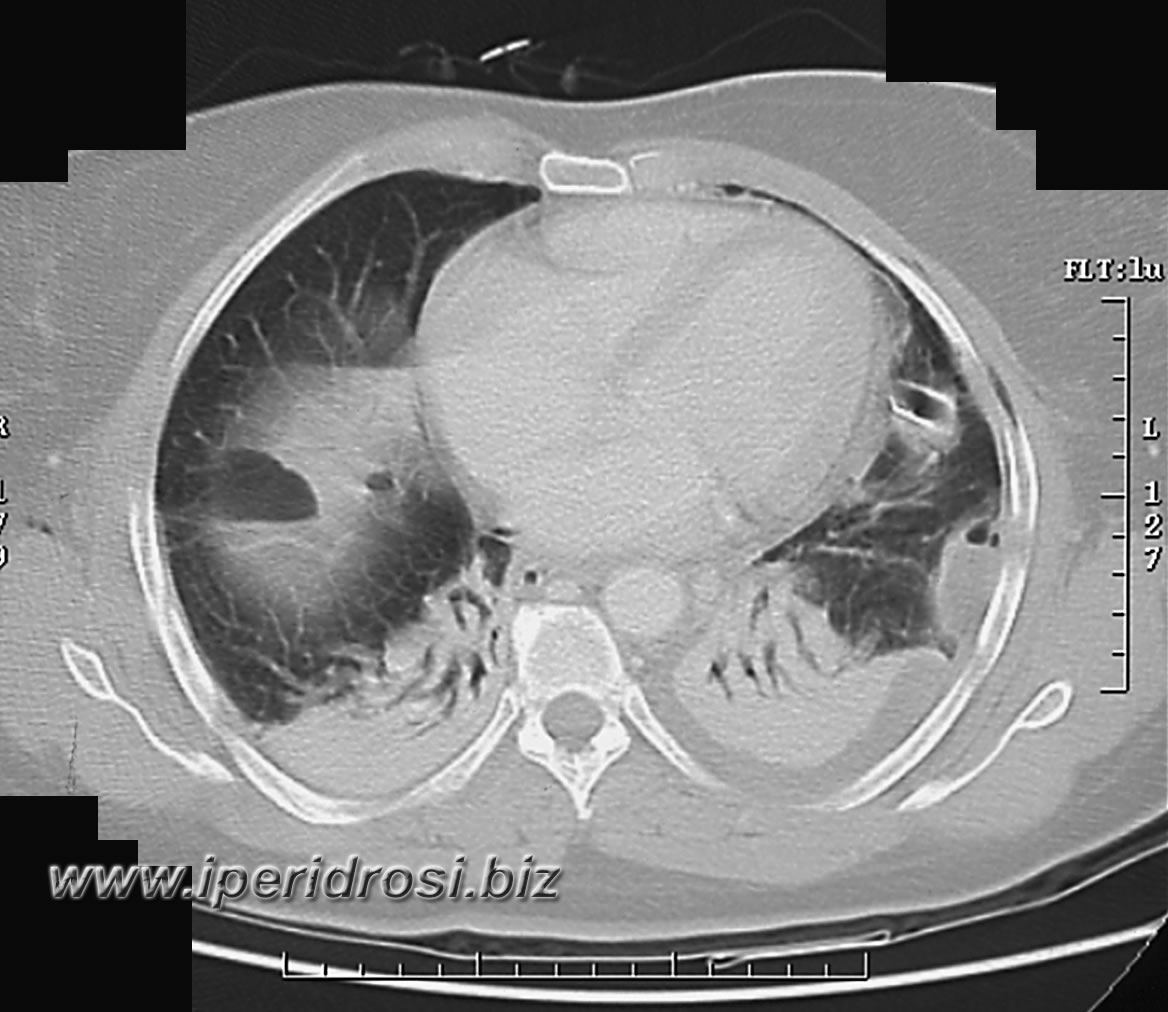

Torace: a sinistra abbondante versamento pleurico e parzialmente saccato, atelettasia parenchimale basale bilaterale più evidente a sinistra dove residua limitato parenchima ventilato.

Addome: abbondante versamento addomino-pelvico diffuso con falda aerea piuttosto abbondante all'addome superiore. Rene a ferro di cavallo con cisti parapieliche a sinistra. Distensione del colon da meteorismo ed ispessimento delle pareti intestinali con iperemia di numerose anse.